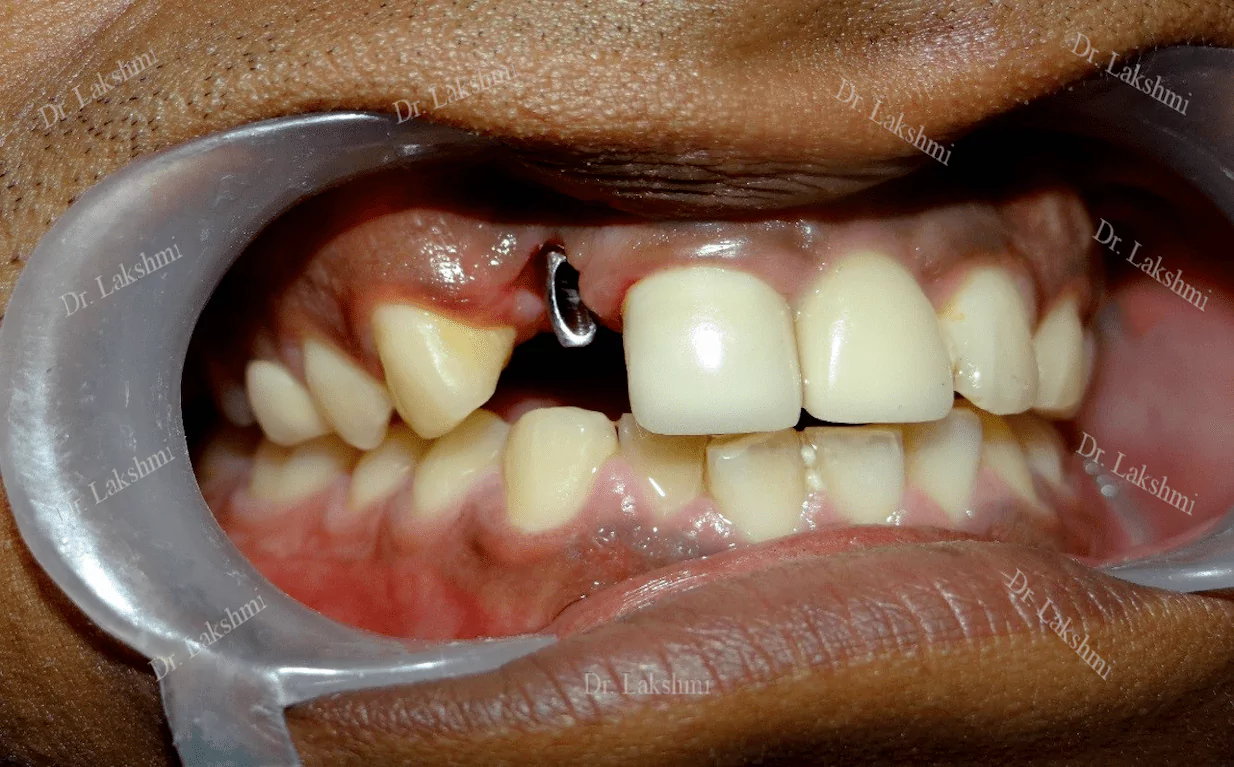

Dental implants have come to define modern dentistry in the last few decades. Dental implants are cemented to the jawbone and an abutment is used as a support for the dental crown that is placed over it. There are a single piece, two-piece and three-piece abutments available for implants. Titanium fuses naturally with the jawbone and that makes it a perfect fit as an implant. There are several dental implant techniques available to opt from, for a patient. The freedom to opt also depends on the condition of the jawbone and the gum.

Requires the placement of a single dental implant (either 2 stage or 1 stage) in the region of the missing tooth, followed by a crown (artificial tooth) over

Treatment Duration: 2 stage dental implants: The replacement is completed in 2 stages which are spread over an interval of minimum 3 months. The first stage involves the placement of the implant and requires one to two sittings,Temporary Crowns will be given to the patient. The second stage involves the placement of the artificial tooth (Permanent crown).

1 stage dental implant: Requires just one stage for the placement of the implant and crown(Permanent Crown).